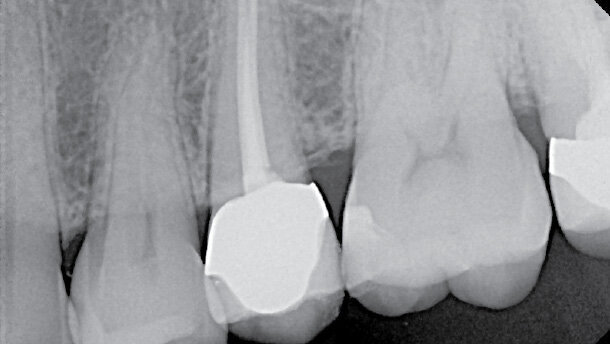

Pacient, jehož snímek je na obrázku 1, byl odkázán na endodontistu, protože prvnímu lékaři se nepodařilo lokalizovat kořenové kanálky.

Pacient trpěl bolestmi zubu 25 při žvýkání a mírnou spontánní bolestí, což vedlo před postoupením případu specialistům k diagnóze nevitální dřeně. Lékař před odesláním pacienta zub otevřel, aniž by lokalizoval kanálek. Poté pacienta předal specialistům. Tato kazuistika se zabývá klinickými nálezy, postupem a potenciálními komplikacemi ošetření případu z pohledu plánování ošetření a pojednává o klinickém postupu a použitých materiálech.

Po předání specialistům byl pacient asymptomatický a bez otoků. Zub byl mírně citlivý na poklep, vyšetření pohmatem, pohyblivost a vyšetření sondou bylo v normě. Z rentgenového snímku byly na zubu 25 zřejmé otevřené okraje korunky a kalcifikované kanálky.

Pokud je trepanační otvor příliš široký, může být ohrožena rezistence keramického pláště korunky – na rtg snímku je patrné, že zub 25 je opatřen metalokeramickou korunkou.

Obr. 1: Klinický případ (zub 25) před zákrokem praktického zubního lékaře